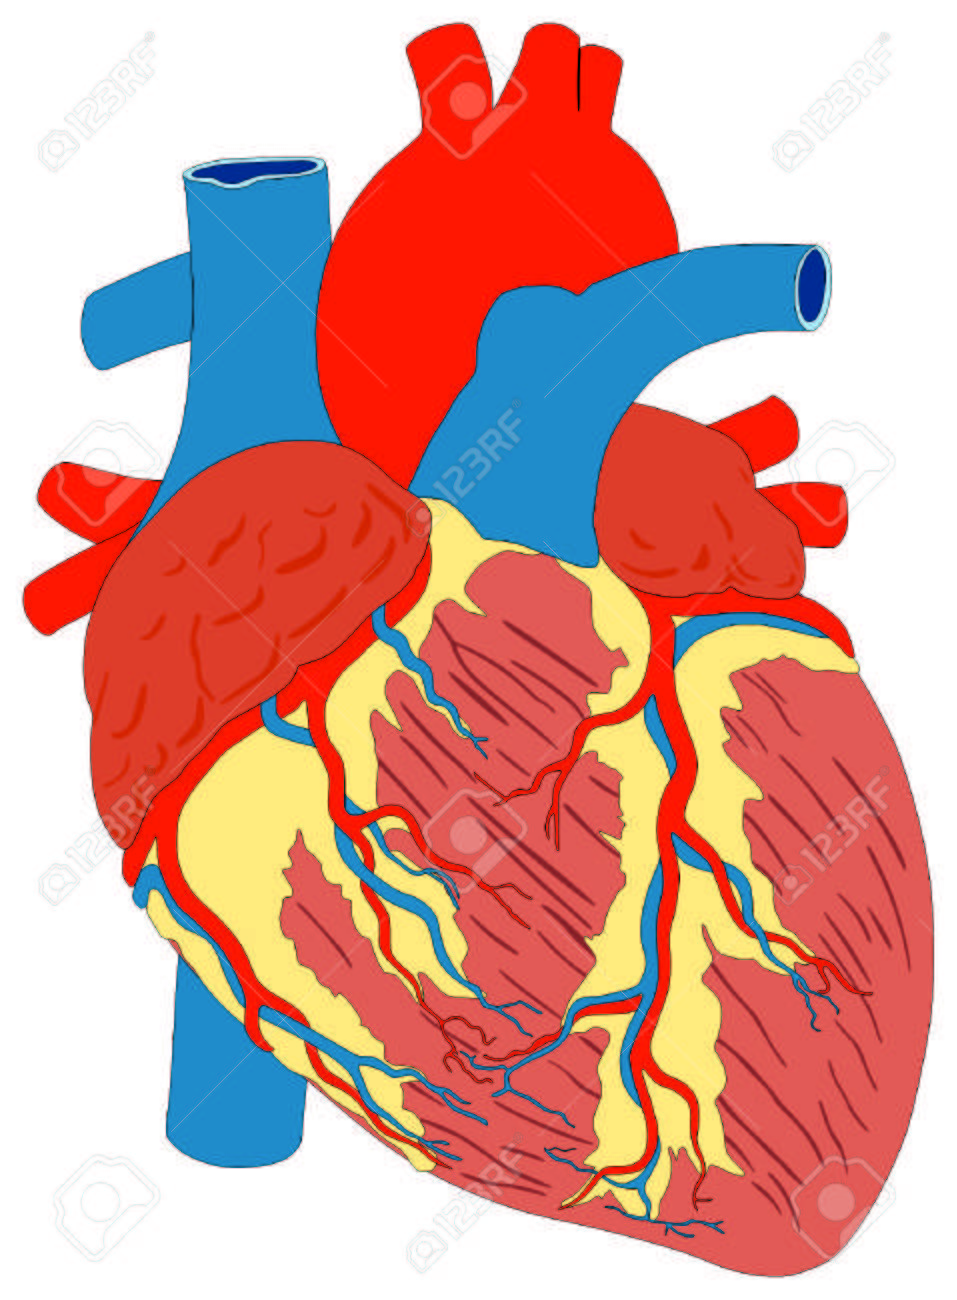

جهاز النقل أو الجهاز القلبي الوعائي هو الجهاز الذي ينقل بواسطة الدم المغذيات، الغازات، والفضلات من وإلى الخلايا، يساعد على مواجهة الأمراض واستقرار حرارة الجسم ودرجة الحموضة pH للحفاظ على حالة الثبات Homeostasis. في حين أن الإنسان كغيره من الفقاريات لديه جهاز نقل مغلق (أي أن الدم لا يغادر أبدا شبكة الشرايين، الأوردة والشعريات الدموية)، بعض مجموعات اللافقاريات لديها جهاز دوران مفتوح. وإن الشعبة الأكثر بداءة لدى الحيوانات لا تملك جهازا للدوران.

جهاز النقل في المخلوقات الحيّة مسؤول عن نقل الموادّ من الأجهزة التي تستوعبها إلى الخلايا، على سبيل المثال: الغذاء من الجهاز الهضمي والأوكسجين من جهاز التنفّس في الإنسان وفي الحيوانات. جهاز النقل مسؤول أيضًا عن نقل الموادّ من الخلايا إلى الأجهزة التي تطلقها خارجًا، كجهاز الإفراز في الإنسان، وعن نقل الموادّ التي تتكوّن في الخلايا إلى خلايا أخرى في الجسم، وهناك تقوم بنشاطها وتساعد في الوساطة والتنسيق بين أجهزة الجسم، على سبيل المثال: الهورمونات.

مكونات جهاز النقل